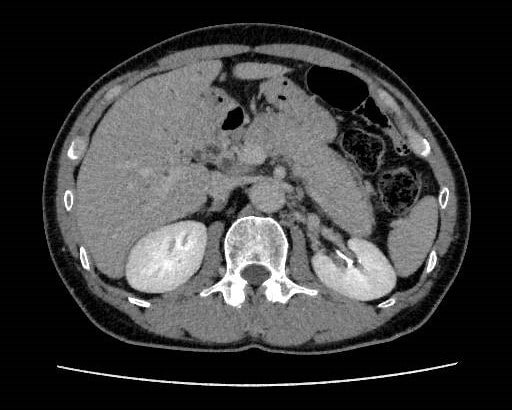

健診にて肝機能異常、皮膚黄染を認め、精査目的で当院消化器内科受診となった。今回実施されたdynamic CTではIgG4関連疾患を疑う所見が認められた。血液検査でもIgG4高値を示しており、IgG4関連硬化性胆管炎と自己免疫性膵炎が疑われ、ステロイドでの加療が開始された。

IgG4関連疾患とは血清IgG4高値とIgG4陽性形質細胞の浸潤、線維化による臓器の腫瘤性、肥厚性病変を呈する全身性慢性疾患である。診断は臨床的及び画像学的診断、血清学的診断、病理学的診断によって行われる。今回実施されたdynamic CTでは胆道狭窄と膵臓のびまん性腫大、膵辺縁部の被膜様構造の所見があり、IgG4関連疾患の診断に有用であったといえる。